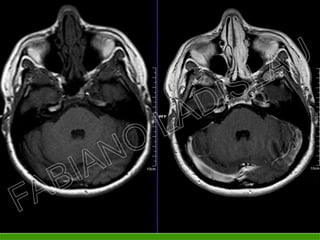

• Tumores e metástases;

• Reações inflamatórias e

processos infecciosos;

• Placas de esclerose ativas;

• Pós-operatório;

• Estudos vasculares (angio-

RM) e estudos perfusionais.